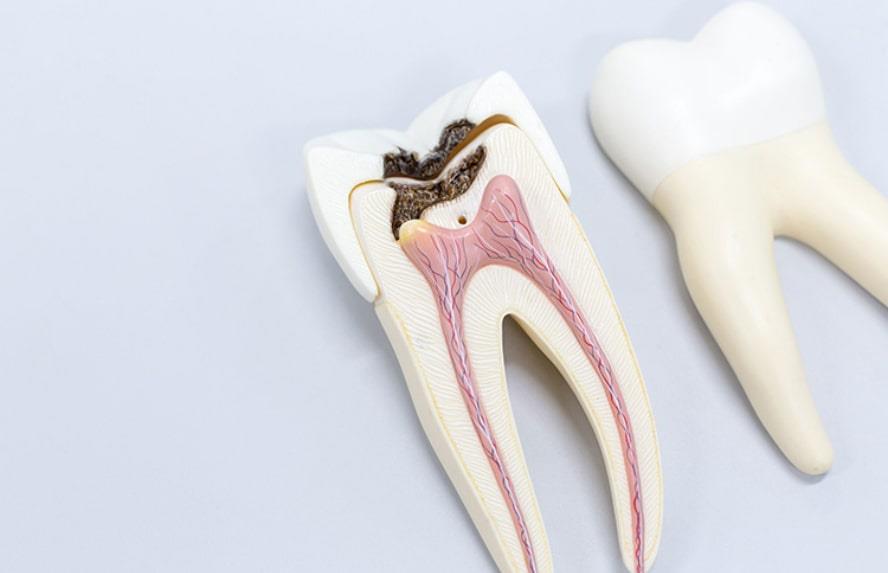

پالپ دندان داخلیترین لایه و بخش دندان است که شامل اعصاب، رگهای خونی، سلولها و بافتهای همبند میشود. این بخش از دندان مواد مغذی لازم برای آن را تأمین کرده و بهنوعی دندان شما را زنده نگه میدارد. لایههای بیرونی دندان چون عاج و مینا، از پالپ دندان محافظت میکنند، اما عواملی مانند پوسیدگی، ترکخوردگی یا دندانقروچه مزمن میتوانند باعث نمایان شدن پالپ و التهاب شدید آن شوند. در چنین شرایطی، ممکن است نیاز به روش خاص درمانی برای کاهش التهاب داشته باشید.

- تولید عاج: پالپ دندان لایه میانی دندان (عاج) را تولید میکند که مینای دندان را حمایت کرده و از خود پالپ نیز محافظت میکند.

- تأمین مواد مغذی: پالپ دندان پروتئینهایی مانند آلبومین و فیبرینوژن تولید میکند تا عاج را سالم نگه دارد.

- مرطوب نگه داشتن دندان: رگهای خونی پالپ به حفظ رطوبت دندان کمک میکنند و از شکنندگی آن جلوگیری میکنند.

عواملی مانند پوسیدگی و ترکخوردگی میتوانند پالپ دندان را در معرض محیط خارجی و عوامل آسیبرسان قرار دهند که باعث عفونت میشود. در صورت عدم درمان، این عفونت میتواند به سایر بخشهای دهان و بدن گسترش یابد. مراحل پیشرفت عفونت پالپ دندان عبارتاند از: